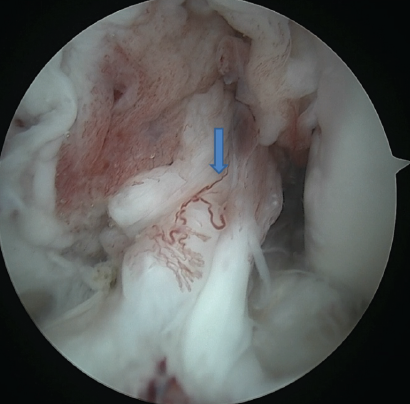

A simple and inexpensive technique was used for outside-in stitches. An 18-gauge spinal needle, which is pre-loaded with no.1 polydioxanone (PDS), is inserted into the joint cavity from outside to inside and passed through the upper surface of the meniscus. For a medial meniscus tear, the viewing portal is the anterolateral portal, and instrumentation is through the anteromedial portal. For a lateral meniscus tear, it is usually the opposite. However, the versatility of changing the portals or even an additional trans-patellar tendon portal is often necessary. Once the PDS is successfully inserted into the joint through the 18-gauge needle, it is retrieved through the anteromedial portal. A simple knot is made with the end of the PDS through which a No. 0 FiberWire is passed. The PDS from the side of the joint is pulled back. Along with the PDS, the FiberWire gets railroaded across to the side of the joint. The spinal needle was inserted again through the same skin puncture point, changing the direction subcutaneously to ensure the spinal needle passes between the lower surface of the meniscus and tibial plateau. The process is repeated, and both ends of FiberWire are retrieved to the medial side of the joint. A safety incision is made to retrieve both ends of the FiberWire. It is important to ensure that the soft tissue between the 2 ends of FiberWire is cleared to allow the stitch to sit on the capsule. An Aberdeen sliding knot is made and reduced to adequate tightness to ensure that the meniscus tear is closely approximated, but at the same time, avoid over-tightening. Then, subsequent half-hitch knots are made. For the lateral meniscus, the outside-in stitches were applied just anterior to the popliteus muscle. Once both the menisci were well peripheralized, the floppy posterior parts of the menisci were addressed using all-inside stitches. The posterior horn of the lateral meniscus was repaired with three vertical mattress sutures using the all-inside 24° DePuy Mitek device (Truespan meniscal repair system) at an interval of 5–10 mm from each other. Most of the devices come with 18 mm as a pre-set depth on opening the package. In total, 18 mm will be sufficient for most tears except when placing the stitch in the central part of the meniscus. The medial meniscus exhibited a displaced bucket handle tear extending from the body to the posterior horn. Initially, the meniscus was reduced using a trocar. The anterior horn and the body were repaired employing an outside-in technique using an 18-gauge spinal needle and No. 2-0 FiberWire. The posterior horn was repaired with 2 all-inside sutures (12° DePuy Mitek). While repairing the medial meniscus, its paramount to hold the knee in 20–30° of flexion and valgus stress to be provided to open up the medial joint space (Figs. 4 and 5).

Figure 4: Completely reduced medial meniscus tear with a combination of outside-in and all inside stitches (right arrow shows completely reduced and peripheralized meniscus).

Figure 5: Completely reduced lateral meniscus tear with a combination of outside-in and all inside stitches (arrow indicating reduced lateral meniscus).